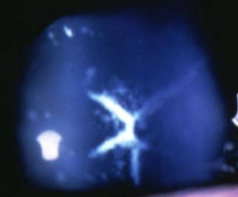

sutural opacities/cataracts

congenital cataract

may be small isolated opacity along the Y suture or dense opacities along partial or total branches of Y sutures

do not progress

found in fetal nucleus

sutural cataract